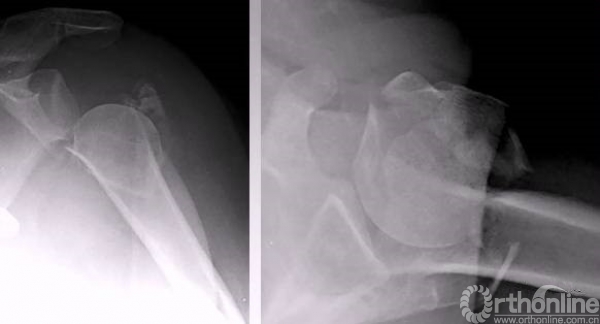

解剖钢板与提拉螺钉的复位

需要注意:不要应用过度提拉,使得内侧肱骨距过复位。

注意完成内侧支撑和内外翻的复位。

在此病例中,为了复位良好,舍弃了肱骨近端与钢板贴服。